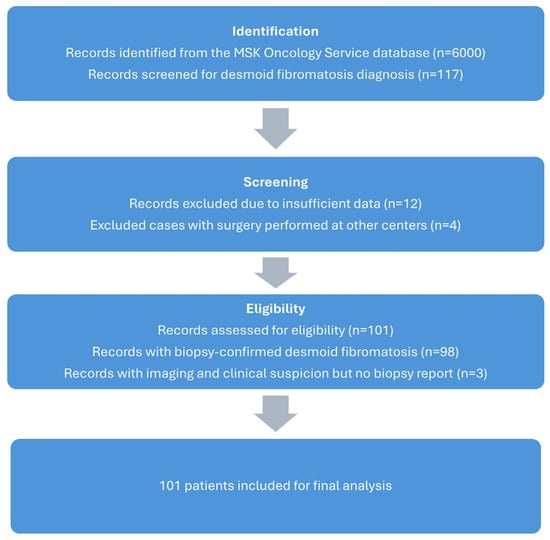

Evaluating Management of Extra-Abdominal Desmoid Fibromatosis: A Retrospective Analysis of Treatments, Outcomes and Recurrence Patterns

Curr. Oncol. 2025, 32(6), 320; https://doi.org/10.3390/curroncol32060320 - 30 May 2025

Background: Desmoid fibromatosis (DF) is a rare, locally aggressive soft tissue tumour with unpredictable clinical behaviour. Historically, treatment has involved surgery; however, contemporary guidelines, such as those from the Desmoid Tumour Working Group, advocate active surveillance. This article reviews current perspectives on DF,

Background: Desmoid fibromatosis (DF) is a rare, locally aggressive soft tissue tumour with unpredictable clinical behaviour. Historically, treatment has involved surgery; however, contemporary guidelines, such as those from the Desmoid Tumour Working Group, advocate active surveillance. This article reviews current perspectives on DF, focusing on epidemiology, pathogenesis, treatment strategies, emerging research directions and cost effectiveness based on our experience at the West of Scotland Musculoskeletal Oncology Service, Glasgow Royal Infirmary (GRI). Methodology: We reviewed 101 patients diagnosed with desmoid fibromatosis between 2010 and 2024. A review of patient records was conducted to gather information on demographics, date of diagnosis, prior treatment, treatment initiation, intervention types, imaging intervals, follow-up duration, recurrence rate for surgery and other intervention, and discharge timelines. All data was systematically organized and analyzed to assess our outcomes. Results: Out of 101 patients with DF in the study, 66% were females. The most common site of primary tumour was lower extremity (39.6%) followed by near equal distribution in upper extremity and trunk. Out of the total cases, 72 (71.2%) were successfully managed with active surveillance involving serial imaging and clinical reviews in accordance with European guidelines. A total of 22 patients (21%) received treatment: 10 underwent surgery alone, 2 had surgery combined with radiotherapy, 8 received only radiotherapy, 1 was treated with hormonal therapy and 1 participated in a trial with Nirogacestat. Of the seven remaining patients, six had unplanned surgery outside followed by active surveillance at GRI. One patient was on alternative treatment modality, homeopathy. The average number of MRI scans per patient was 3.11, with many patients requiring significantly more imaging. MRI surveillance varies significantly in desmoid tumours due to their heterogeneous behaviour. Active or symptomatic tumours often require more frequent scans (every 3–6 months), while stable cases may need only imaging annually or just clinical monitoring. Recurrence was noted in eight patients, all of which were related to prior surgery. The total combined cost of imaging and appointments exceeds £6500 per patient in active surveillance. Conclusions: We conclude that most patients with desmoid fibromatosis in our cohort were effectively treated with active surveillance, consistent with current European guidelines. Surgical management of desmoid fibromatosis in our cohort is historic and has shown a significant recurrence risk. Our study proposes a revised follow-up protocol that significantly reduces costs without compromising on patient care. We suggest a two-year surveillance period for stable disease with patient-initiated return to reduce unnecessary clinic visits, imaging and healthcare costs.